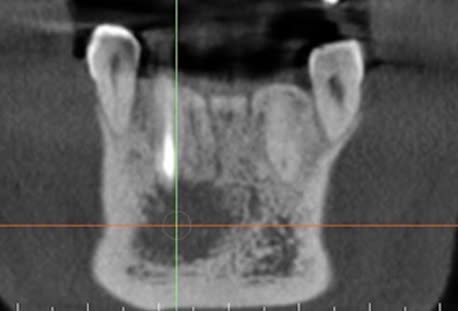

Hình 1. CBCT trước điều trị, bệnh nhân Đ.Q.Q